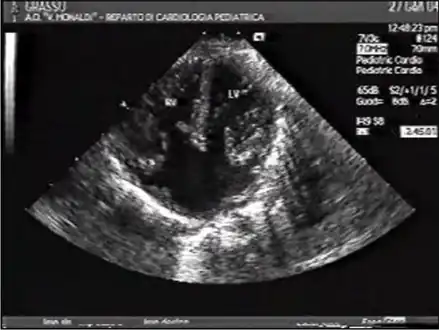

- Ultrasound showing a complete atrioventricular septal defect